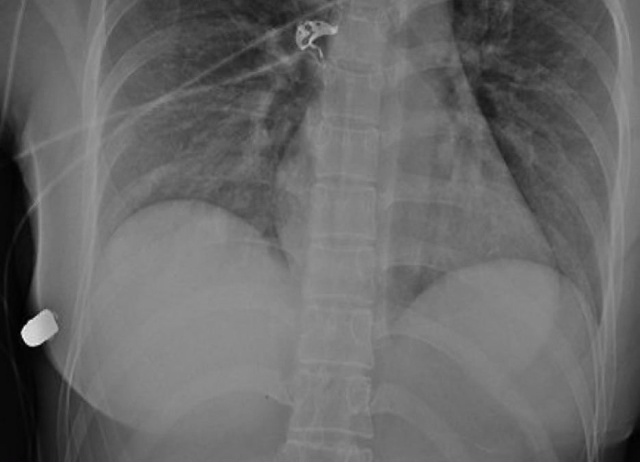

Силиконовый имплант стал настоящим спасителем для девушки, остановив пулю, которая была направлена прямо в её сердце.

Во время обследования врачи обнаружили, что пуля сломала ребро с правой стороны грудной клетки. Удивительно, но она вошла в левую молочную железу и, рикошетом от импланта, попала в правую.

Рентген ранения